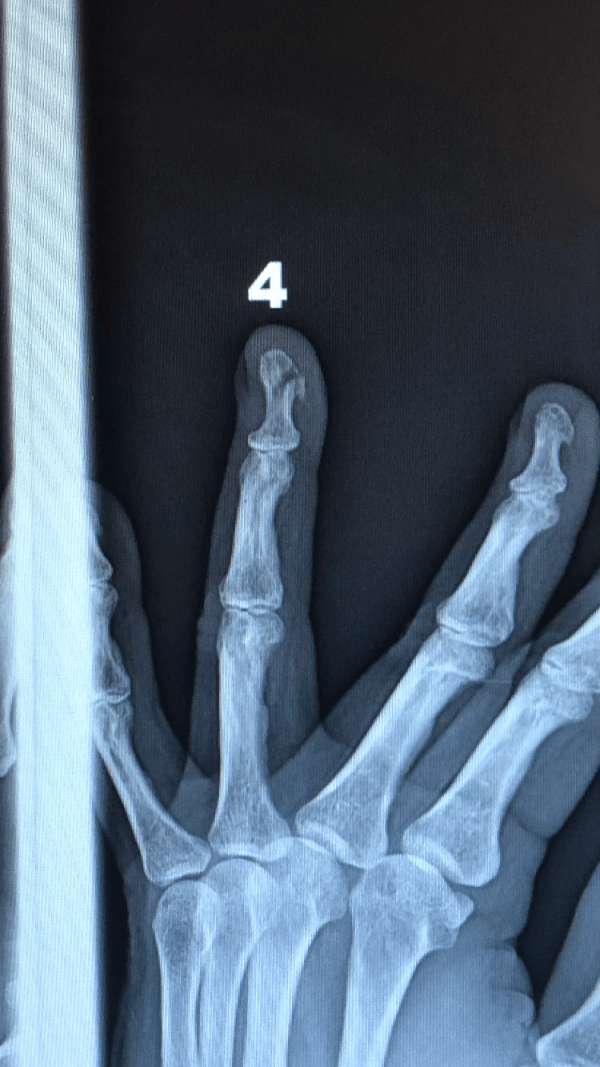

They took X-rays and sure enough, the end of my fourth finger showed a break even I could see on the X-ray. They put a splint on it and sent me home with instructions to see an orthopedic surgeon and I may take Tylenol for the pain.

My understanding is that the end of fingers is made of softer bone and it breaks more easily. It also gets limited blood flow and there is not too much they can do for it.